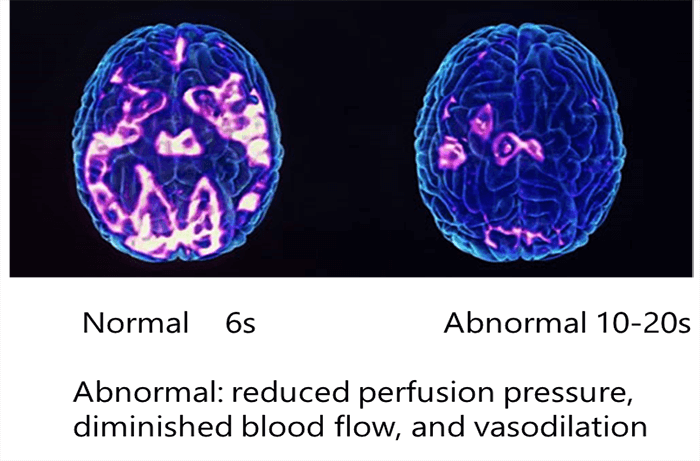

CBV plays an essential role in the assessment of cerebral perfusion disorders.

- Auto-regulatory vasodilation produces an increase in regional CBV; the change may be visible in CT perfusion maps and demonstrate reduced perfusion pressure

- Increased CBV stemming from auto-regulatory vasodilation is relatively small, contributing to a bad visualization of the vessels map

The third main parameter to take into consideration is the Mean Transit Time. MTT is measured in seconds and defined as the average amount of time it takes blood to transit within the blood vessels in a particular region of the brain. In brain imaging, maps of MTT are the most commonly used in clinical situations.

Prolonged MTT value in the context of normal CBF means that the affected tissue could remain in this intermediate state indefinitely without a threat to viability and the appearance of clinical symptoms. Alternatively, if the CBF is low, the integrity of the tissue and the clinical response may be compromised, depending on the severity of the reduction in CBF.

Normally, the abnormal perfusions are easily detected upon visual Tmax. However, severe perturbations in any hemodynamic parameter are associated with abnormalities. Thus all hemodynamic maps must be considered together to make an accurate determination of the risk to the tissue and the patient.